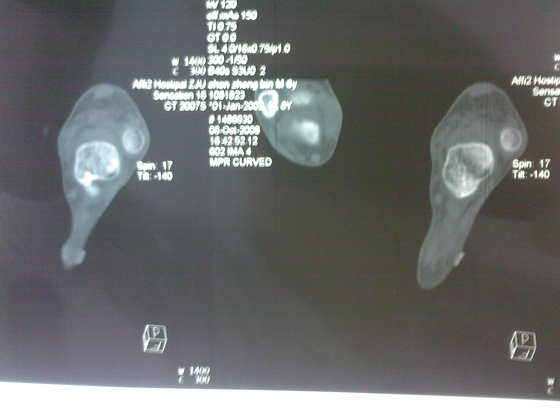

把病理送浙一医会诊后诊断为:骨外软骨瘤。同时做了CT检查。暂未予治疗。

今天把创面情况跟CT发上请大家看看。

继续还有几张。